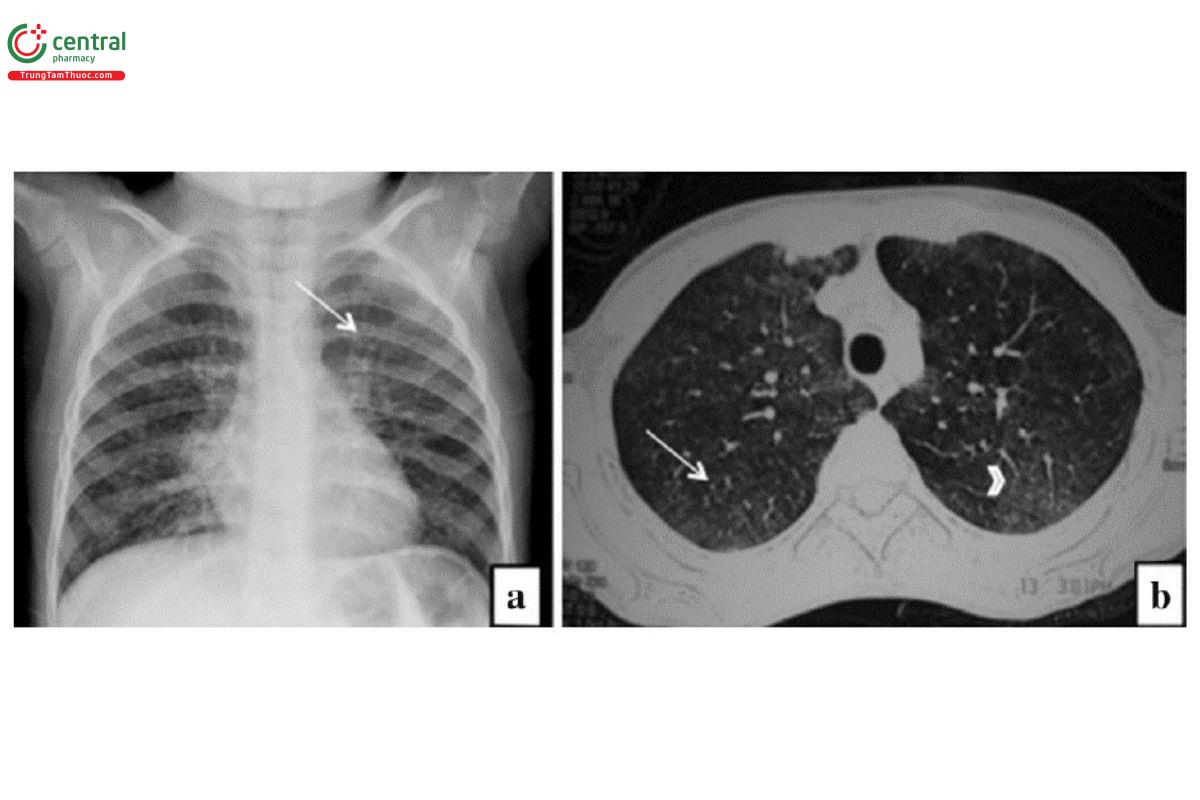

Viêm phổi do Mycoplasma pneumoniae: X-quang ngực thấy các tổn thương mờ dạng lưới hoặc đông đặc [18]. Trên CT, phổ biến là các nốt trung tâm tiểu thùy và các vùng đông đặc từ tiểu thùy đến thùy hoặc hình ảnh kính mờ với dày thành các phế quản trung tâm.

Chú thích: a) Hình ảnh mờ dạng lưới hai bên phổi (mũi tên trắng). b) Hình ảnh các đám mờ dạng kính mờ (đầu mũi tên) và các nốt mờ bờ không rõ ràng ở hai bên phổi (mũi tên trắng)